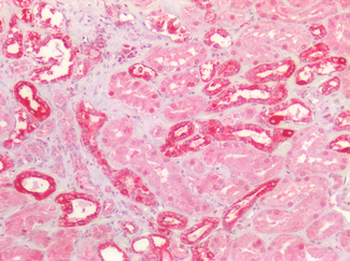

Immunohistochemistry of AXIN2 in mouse lung tissue with AXIN2 antibody at 5 µg/mL.